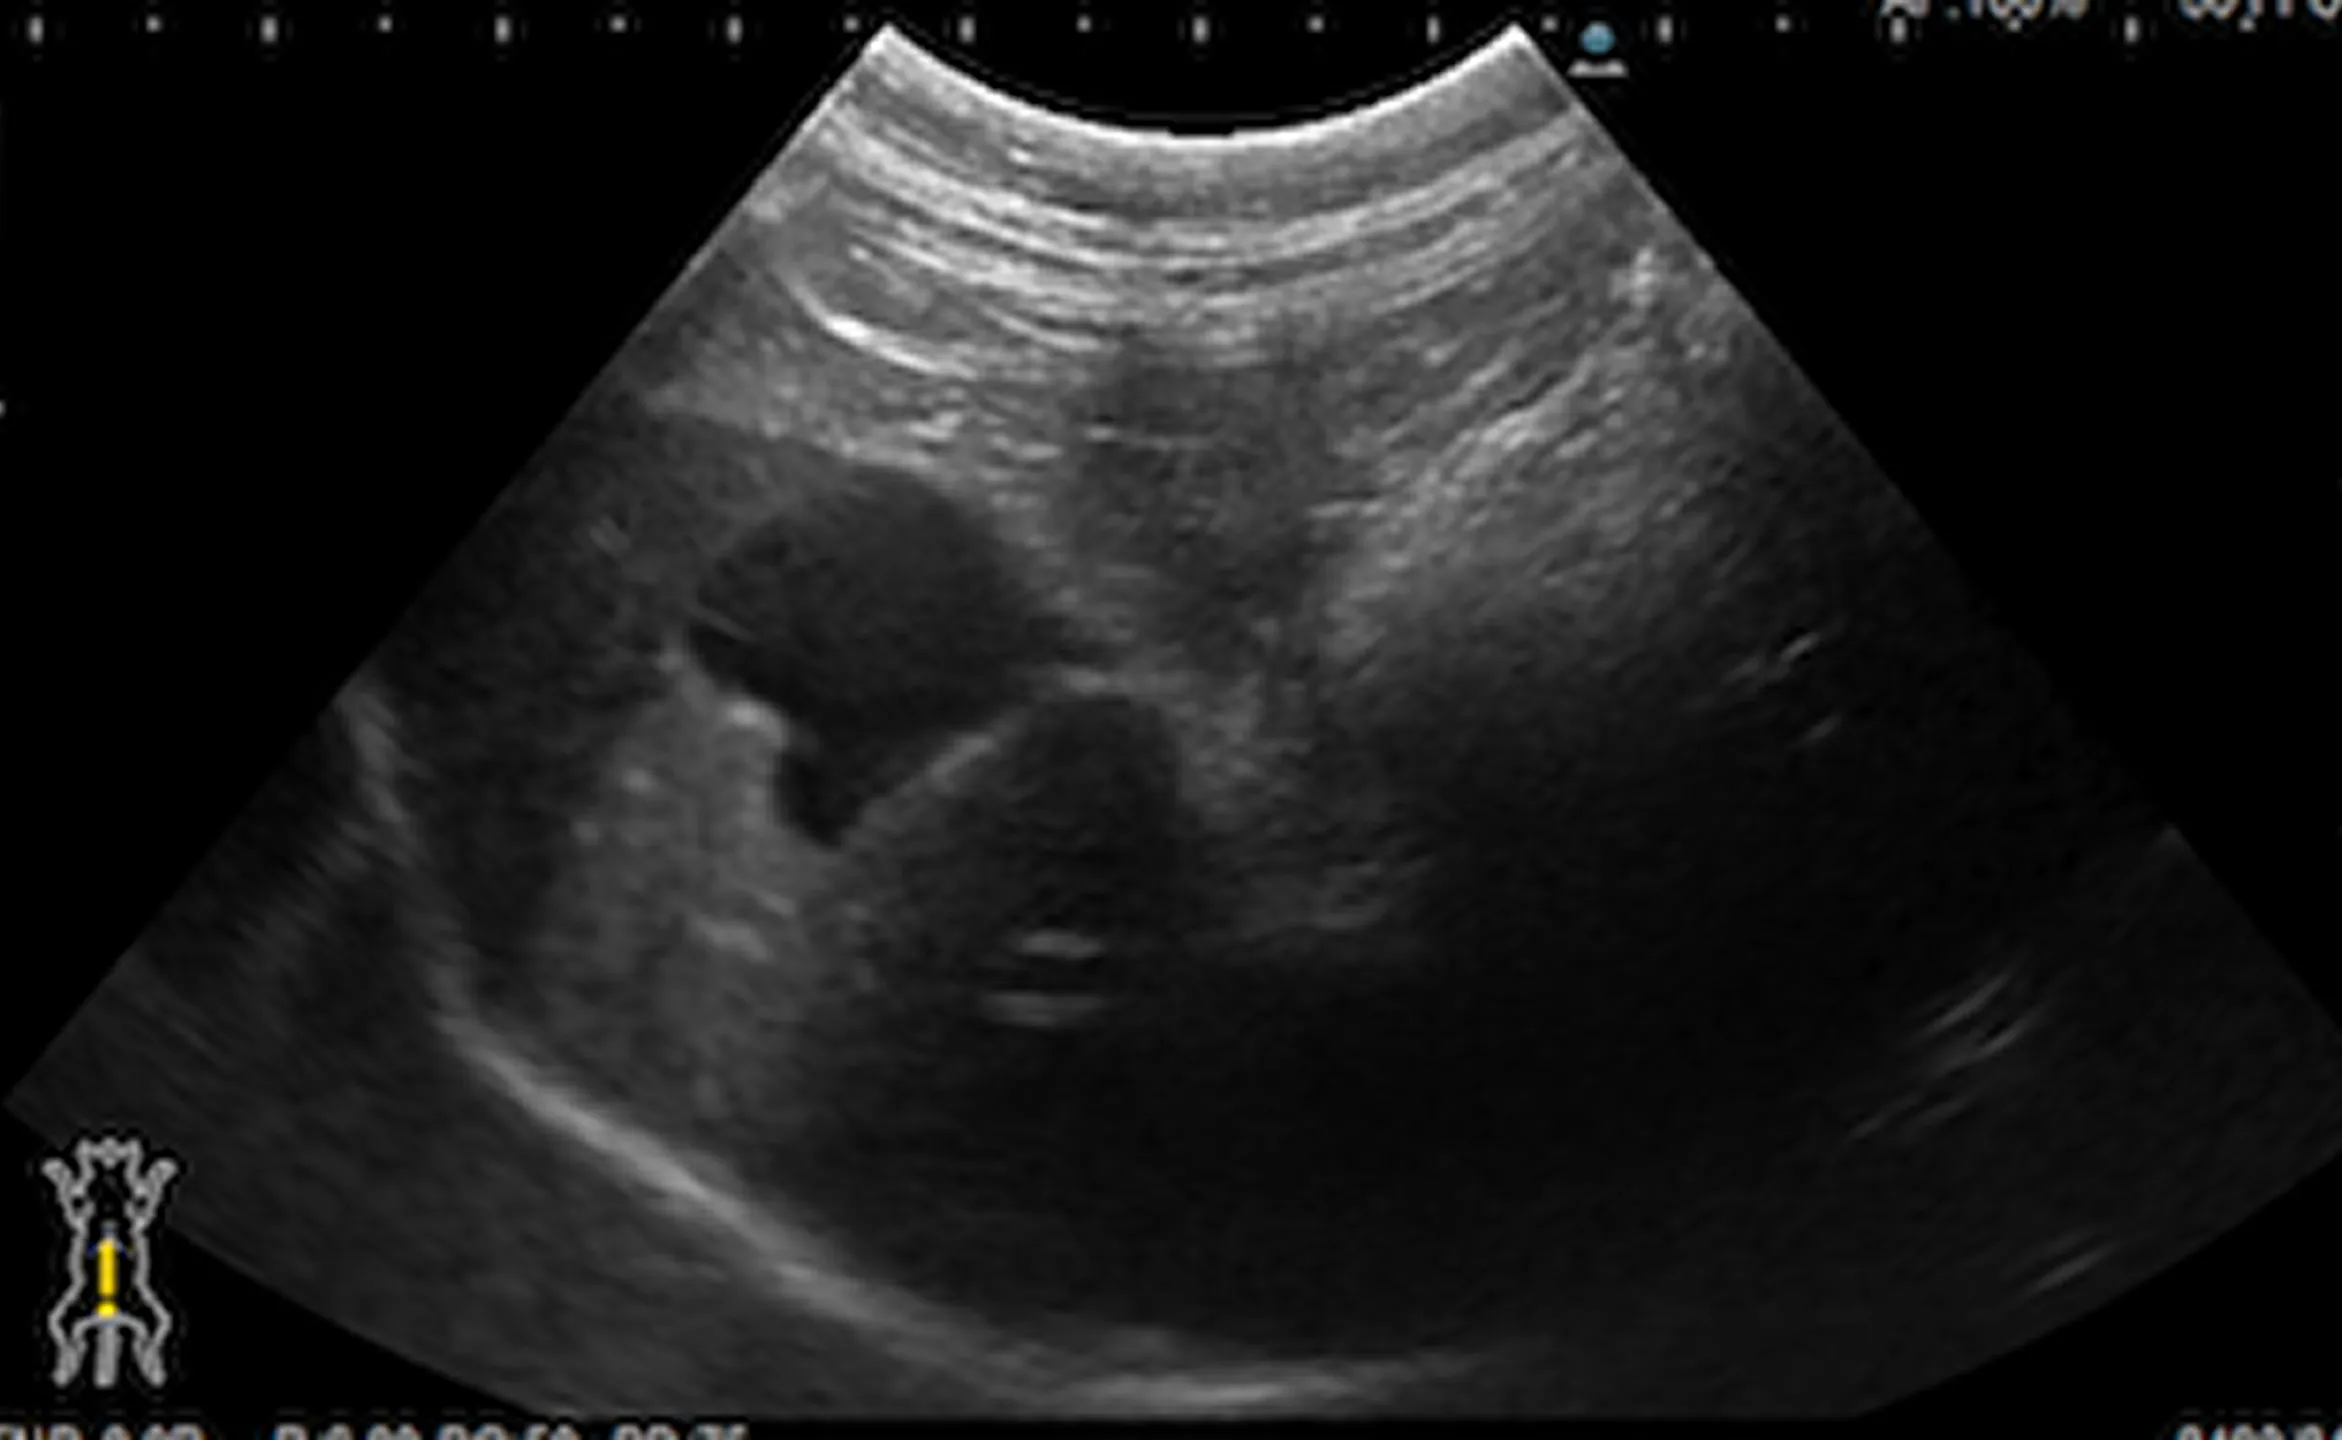

治療前後の超音波検査画像

治療後

腹水は確認できなくなりました。黒く見えているのは胆嚢です。